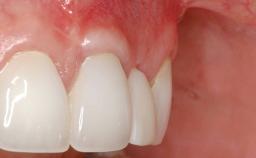

Soft-Tissue Volume Augmentation Using a Connective-Tissue Graft Harvested from the Maxillary Tuberosity

In 1983, a 51-year-old non-smoking patient was referred for the treatment of moderate chronic periodontitis. At the initial examination, 47% of sites exhibited probing depths of 4 to 6 mm. Periodontal therapy consisted of initial periodontal treatment including oral-hygiene instructions and supra- and subgingival debridement, followed by periodontal surgery to eliminate residual pockets.

| Soft Tissue Grafting | Simultaneous |